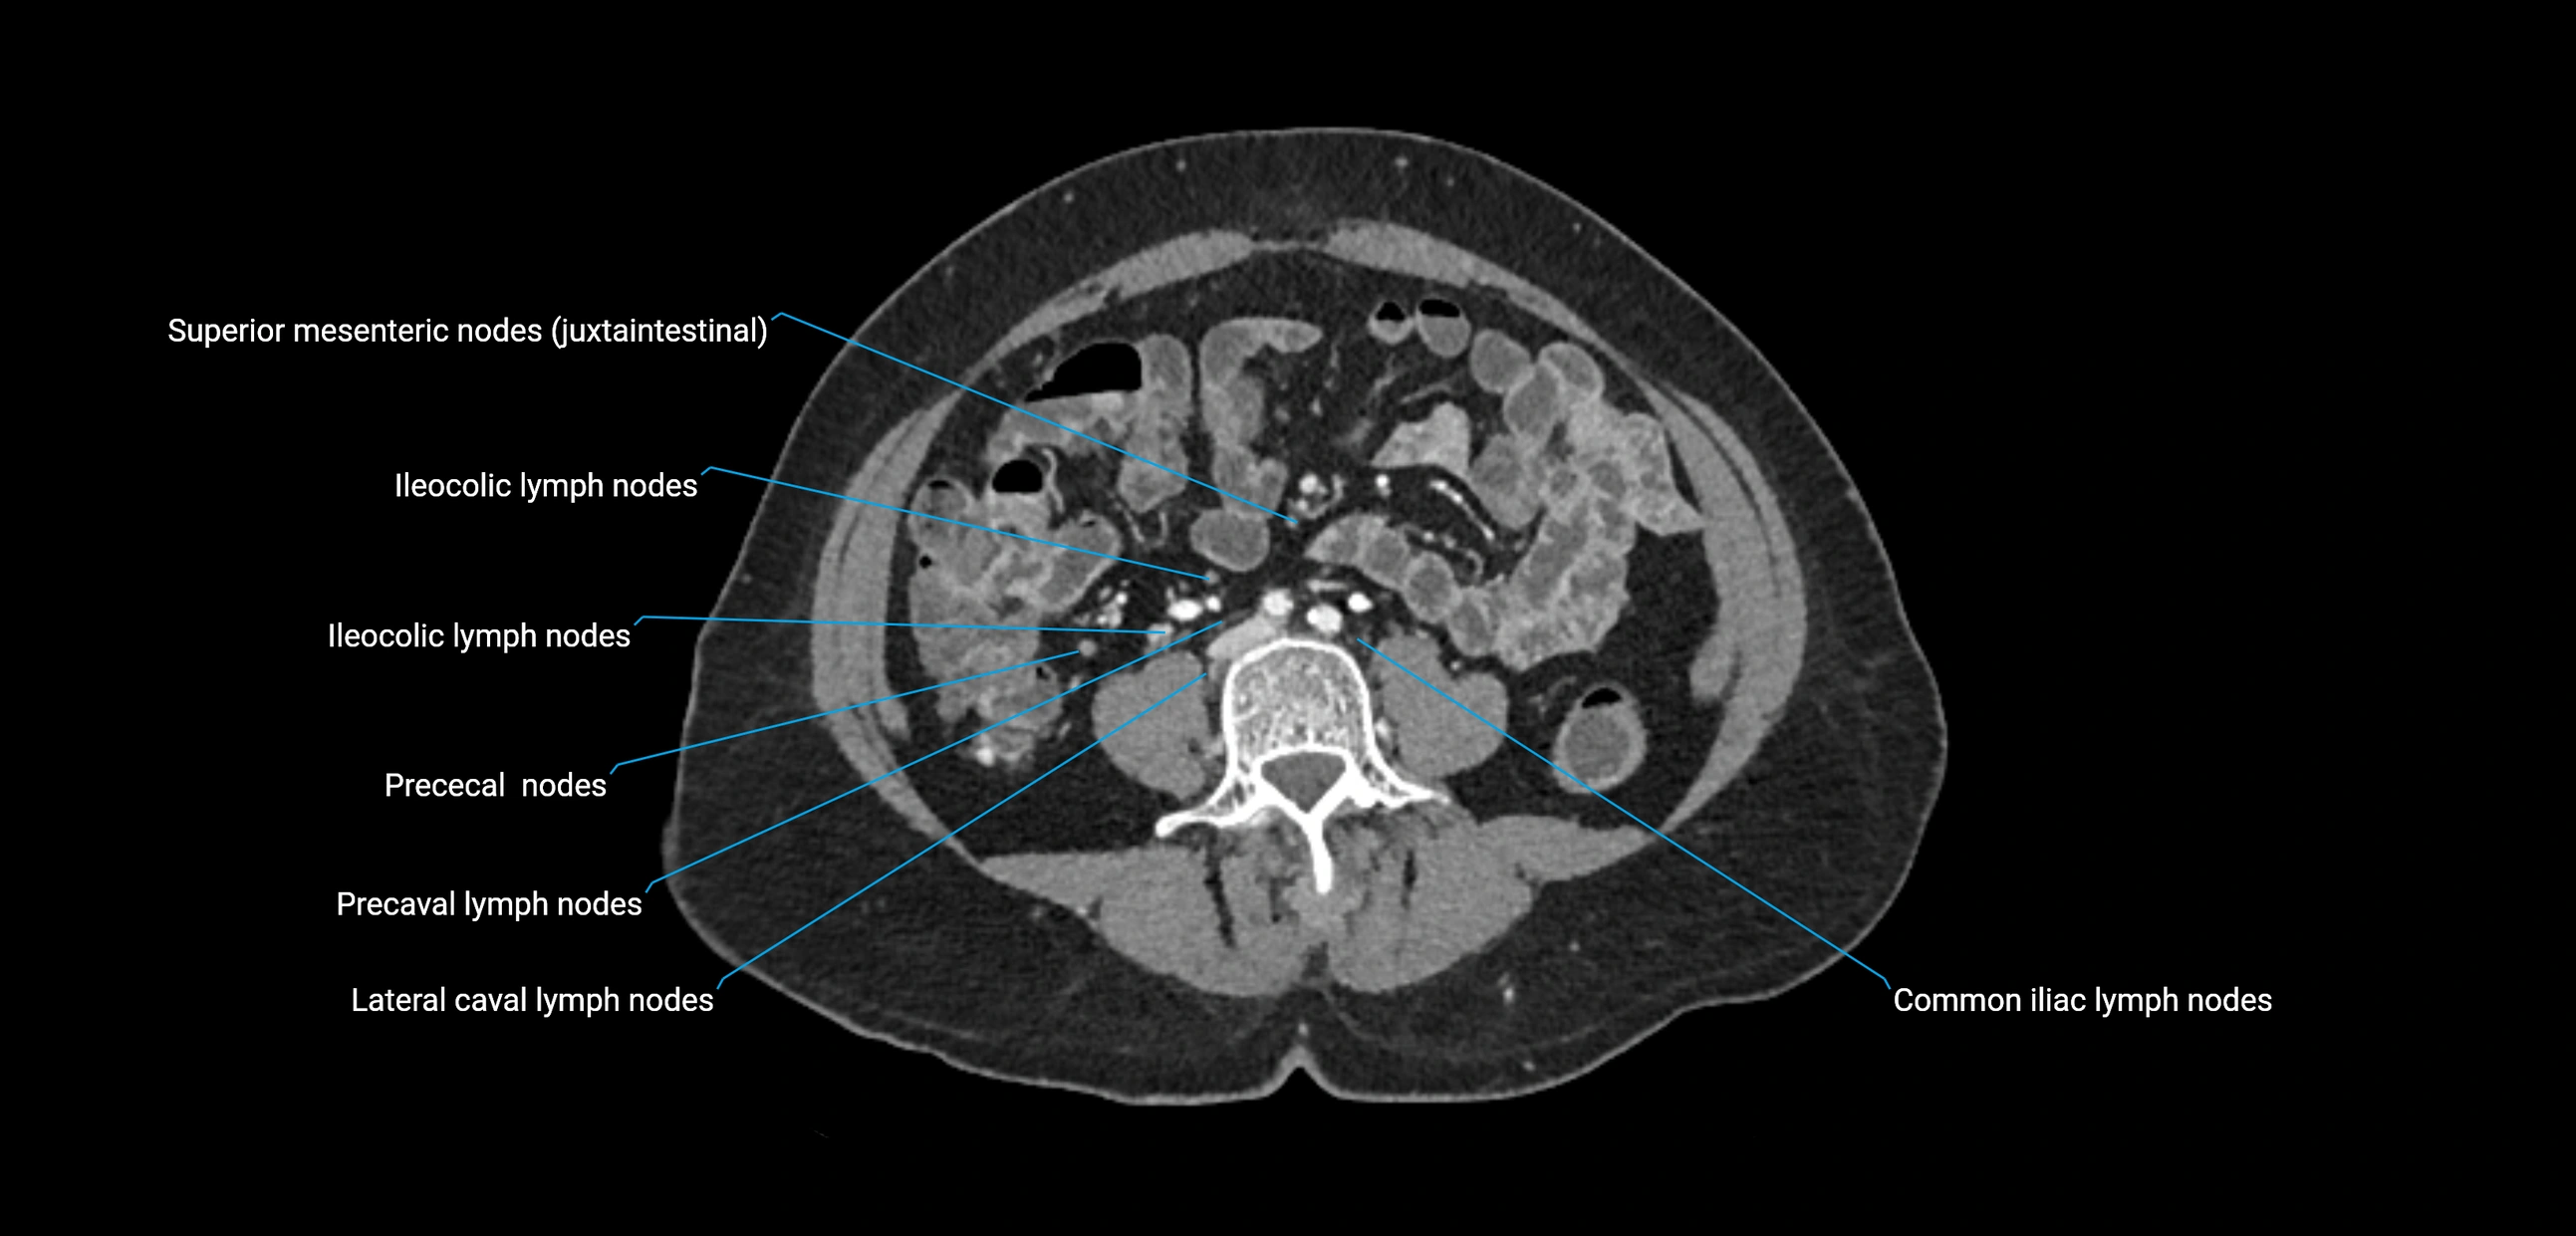

CT Appearance

CT Pre-Contrast:

• Nodes appear as soft-tissue density nodules adjacent to the aorta and IVC

• Calcification may be seen in chronic infections (e.g., tuberculosis)

CT Post-Contrast:

• Normal nodes enhance homogeneously

• Malignant nodes may show heterogeneous enhancement, central necrosis, or conglomerate formation

• Size >1 cm short axis is suspicious, though morphology and distribution are equally important